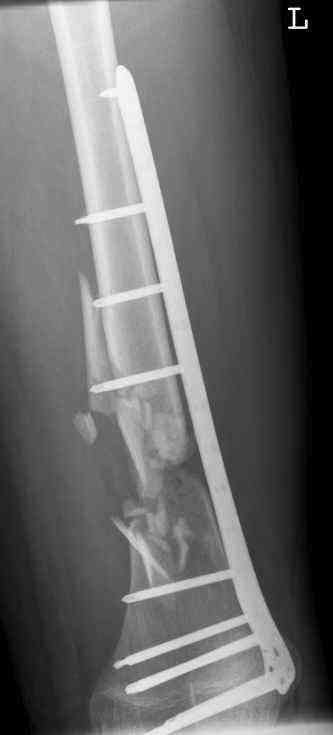

16 yr old boy, high energy motorcycle trauma trauma in July 2005 with:

- hip dislocation + acetabular fracture L

- distal femoral fracture L

- tibial shaft fracture L

- metatarsal fractures L

Feb 07

feb 07: retrograde nail + bone graft + BMP

may 07: dynamisation nail

sept 07: locking screw removal (max. dynamisation reached)

nov 07: persistant non-union distal femur; other fractures healed uneventfully.

All with gradual/partial weightbearing etc. Currently 50-100% weight bearing, no pain.

Soft tissues are intact. No smoking or diabetes. CRP <2

What would you do?